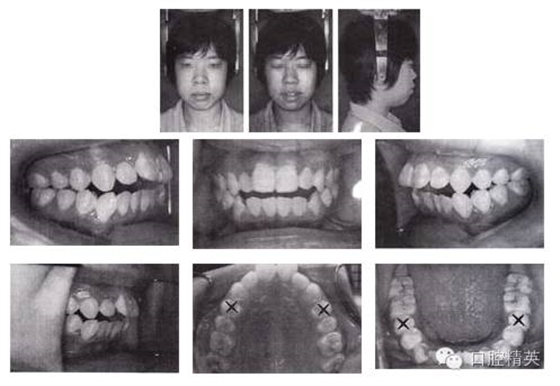

姓名:蘇某 年齡:18歲 性別:女

主訴:口唇前突、開頜,求矯治。

檢查:恒牙列,雙側磨牙中性偏遠中關系,11、12 、13 、21、22 、23中度開頜,上下頜牙列輕度擁擠。正面觀,面型左右對稱;側面觀,雙頜前突,明顯開唇露齒,下頜頦部發(fā)育不良致后縮。顳下頜關節(jié)無異常。

圖3-1 矯治前面像及口內(nèi)像(開始矯治 2002-08-25)